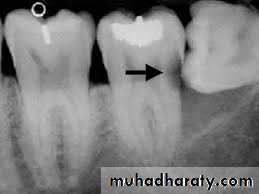

3. Radiography method

Types of X-ray radiograph images:• Periapical X-ray radiograph.

• Bitewing X-ray radiograph.

• Panoramic X-ray radiograph.